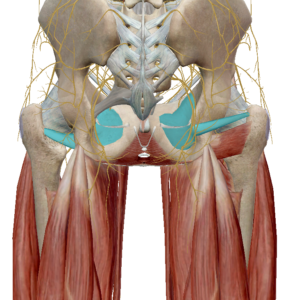

2) 골반

(1) 장골근

장골근은 장골의 안쪽 면에서 시작하여 대퇴골 소전자에 연결됩니다.

장골근이 수축하면 골반의 전방경사와 고관절 굴곡이 발생합니다.

(2) 대둔근

대군근은 장골과 엉치뼈를 지나며 대퇴골에 연결되어 있습니다.

고관절의 신전과 외회전을 발생시킵니다.

(3) 중둔근과 소둔근

중둔근은 고관절 측면 안정성에 중요한 근육입니다.

수축 시 고관절 외전과 섬유의 위치에 따라 내회전과 외회전도 관여한다고 합니다.

소둔근도 중둔근과 같이 고관절 측면 안정성에

중요한 역할을 합니다.

고관절 외전을 발생시키며 고관절 앞쪽에 연결되어 있어 고관절 굴곡과 내회전을 발생합니다.

(4) 이상근

이상근은 천골의 앞쪽에서 부터 대퇴골의 위쪽을 향하고 있습니다.

고관절을 외회전 시키며 이상근 아래로 좌골신경이 지나가면서 좌골신경통의 원인으로 주목받고 있습니다.

이상근이 주목받는 또 다른 이유로는 기능의 변화입니다.

이상근은 고관절이 90도 이상 굴곡될 경우 고관절 내회전으로 기능이 변화합니다.

이는 근육의 기능은 해부학적 자세에서 기록된 것이며 자세에 따라 다르게 작용할 수 있다는 근거가 됩니다.

(5) 쌍자근

쌍자근은 고관절의 심부 외회전근육으로 상쌍자근과 하쌍자근이 존재합니다.

좌골에서 대퇴골 후면으로 이어져 고관절의 외회전 기능을 발생합니다.

(6) 대퇴방형근

대퇴방형근은 좌골과 대퇴골을 연결하는 근육으로

수축 시 고관절의 외회전을 발생합니다.

(7) 폐쇄근

폐쇄근은 골반의 폐쇄공에서 시작하여 대퇴골로 연결된 근육입니다.

외폐쇄근과 내폐쇄근이 있으며 수축 시 고관절의 외회전을 유발합니다. (왼쪽 : 외폐쇄근 / 오른쪽 : 내폐쇄근)